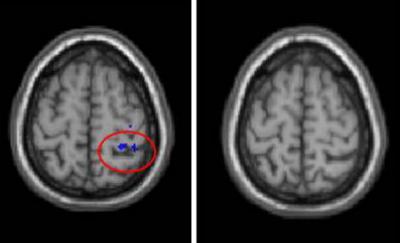

Researchers then used a functional MRI to image the blood-oxygen levels in different parts of the brain, a measurement of brain activity.

"The more they recruited the other side of the brain, the slower they responded," Seidler said.